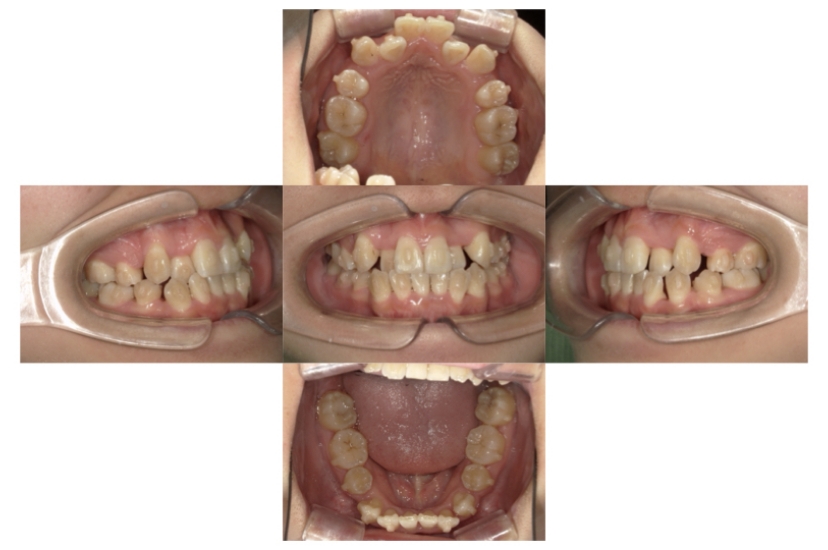

症例1

上顎前突、叢生

抜歯

ブラケット矯正

上下顎叢生、上顎前突(出っ歯、上下の前歯のガタガタ)のケースです。

装置はラビアル(上下表側)で、上顎の小臼歯を2本抜歯を行っています。抜歯したスペースを使って、上の前歯の後方移動と叢生(ガタガタ)と出っ歯の改善を行っています。下は歯と歯の間にIPR(隣接面削合)を行い、スペースを確保し、叢生の改善を行っています。

主訴 前歯のガタガタと出っ歯が気になる。

年齢・性別 47歳 女性

お住まいの地域 神奈川県川崎市

治療方針 抜歯スペースおよびIPRを利用して上前歯の叢生(ガタガタ)の改善

抜歯部位 上顎左右第一小臼歯

使用装置 ラビアル(上下表側)、顎間ゴム

治療期間 2年0か月

治療回数 15回

リテーナー クリアリテーナー

BEFORE

AFTER